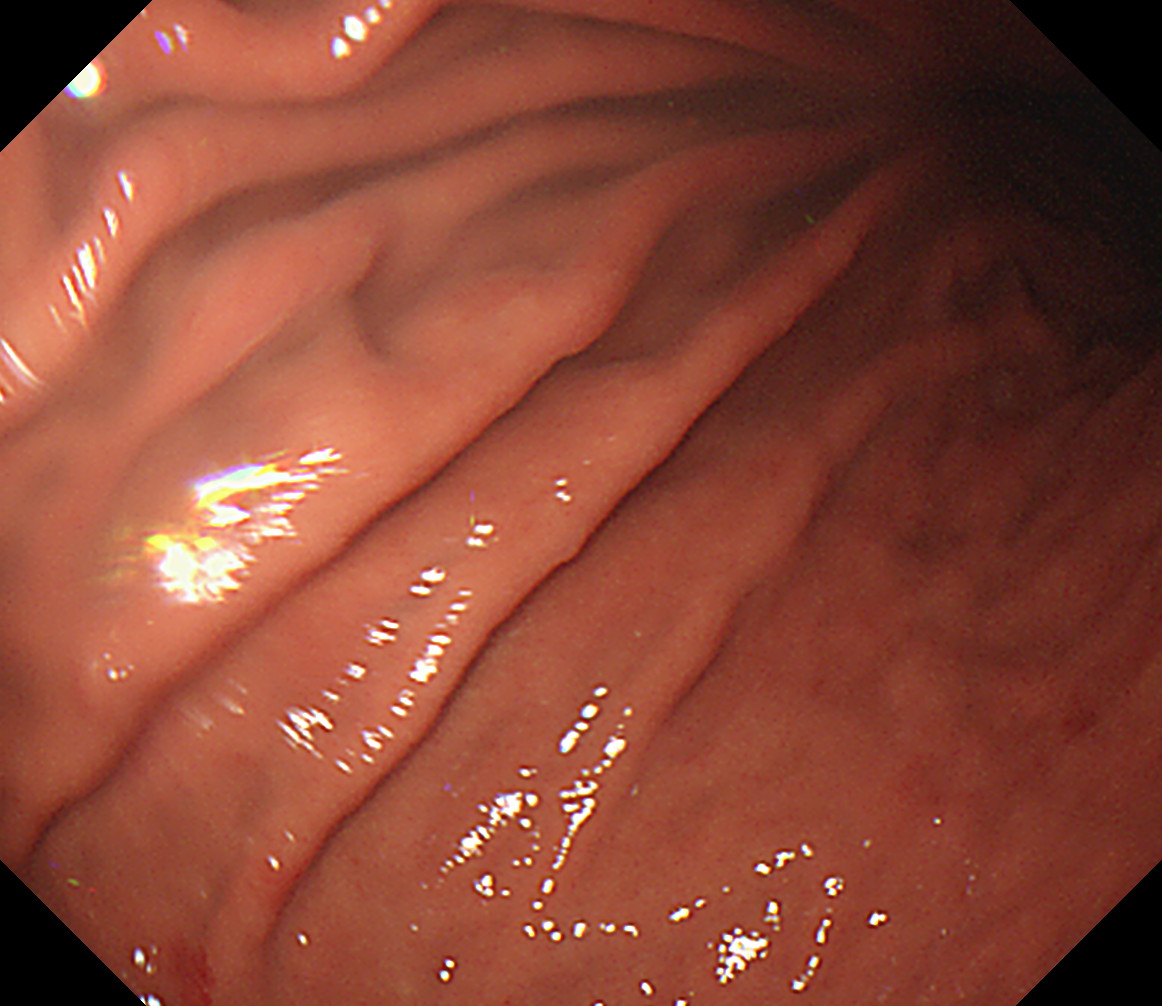

24 体下部後壁 引き上げて

後壁から反時計回り

接線になり見逃しやすい部位です

体下部後壁